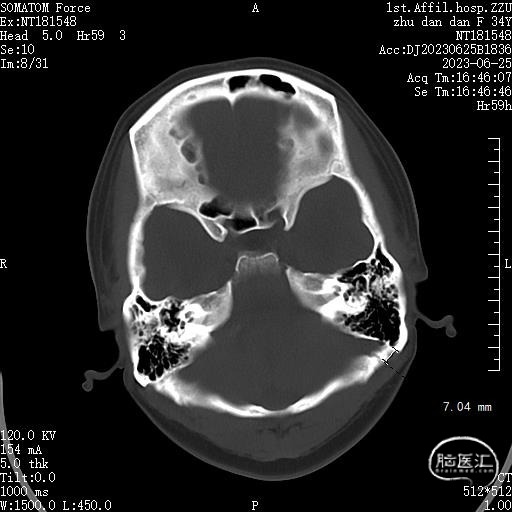

术前CT:乳突气化良好,后颅窝空间狭小

术前MRI:可见面神经REZ区有血管影,但是其信号与动脉信号有区别。同时因后颅窝解剖结构变异,乙状窦位置可能影响CPA区暴露